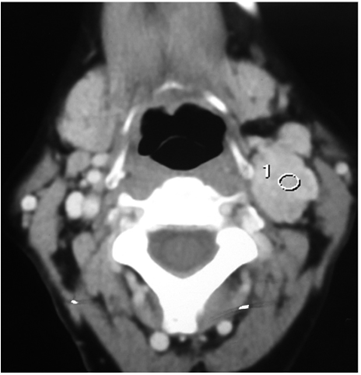

Hombre de 56 años, sin antecedentes de importancia, que consultó por aparición de una masa en el espacio vascular cervical izquierdo, de mínimo crecimiento y sin síntomas asociados. El examen físico de la orofaringe mostró mínima compresión del espacio para-faríngeo y la evaluación del cuello reveló signos de Chevassu y Fontaine presentes, con una masa de 6 cm. Se realizó angiotomografía de vasos cervicales (figuras 3 y 4) que informó un glomus carotideo izquierdo Shamblin III, con posible invasión endoluminal, por lo cual, antes de la cirugía, se realizó un test de oclusión carotidea.